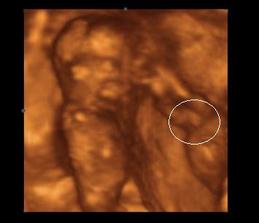

Mozno fazulka, z ktorej sa vykluli hned dve fazulky.

23.11. (13tt+4) sme boli na nasom prvom 3D. Drobciatka sa nam krasne predviedli a poukazovali. A mali uzasne rozmery. Jeden mal 8,19cm a druhy 7,41cm. No nie su super :o)))

09.11. sme boli na dalsom 3D, kvoli trojnasobnemu AFP. Pán Dr. nam odmeral kazdu kosticku, skontroloval chrbticu, mozocek, srdiecko a vsetko co sa len dalo a povedal, ze drobcekovia su zdravunki :o) Mame 10,51 cm a 9,99 cm. Jo a budu to chlapi!!!